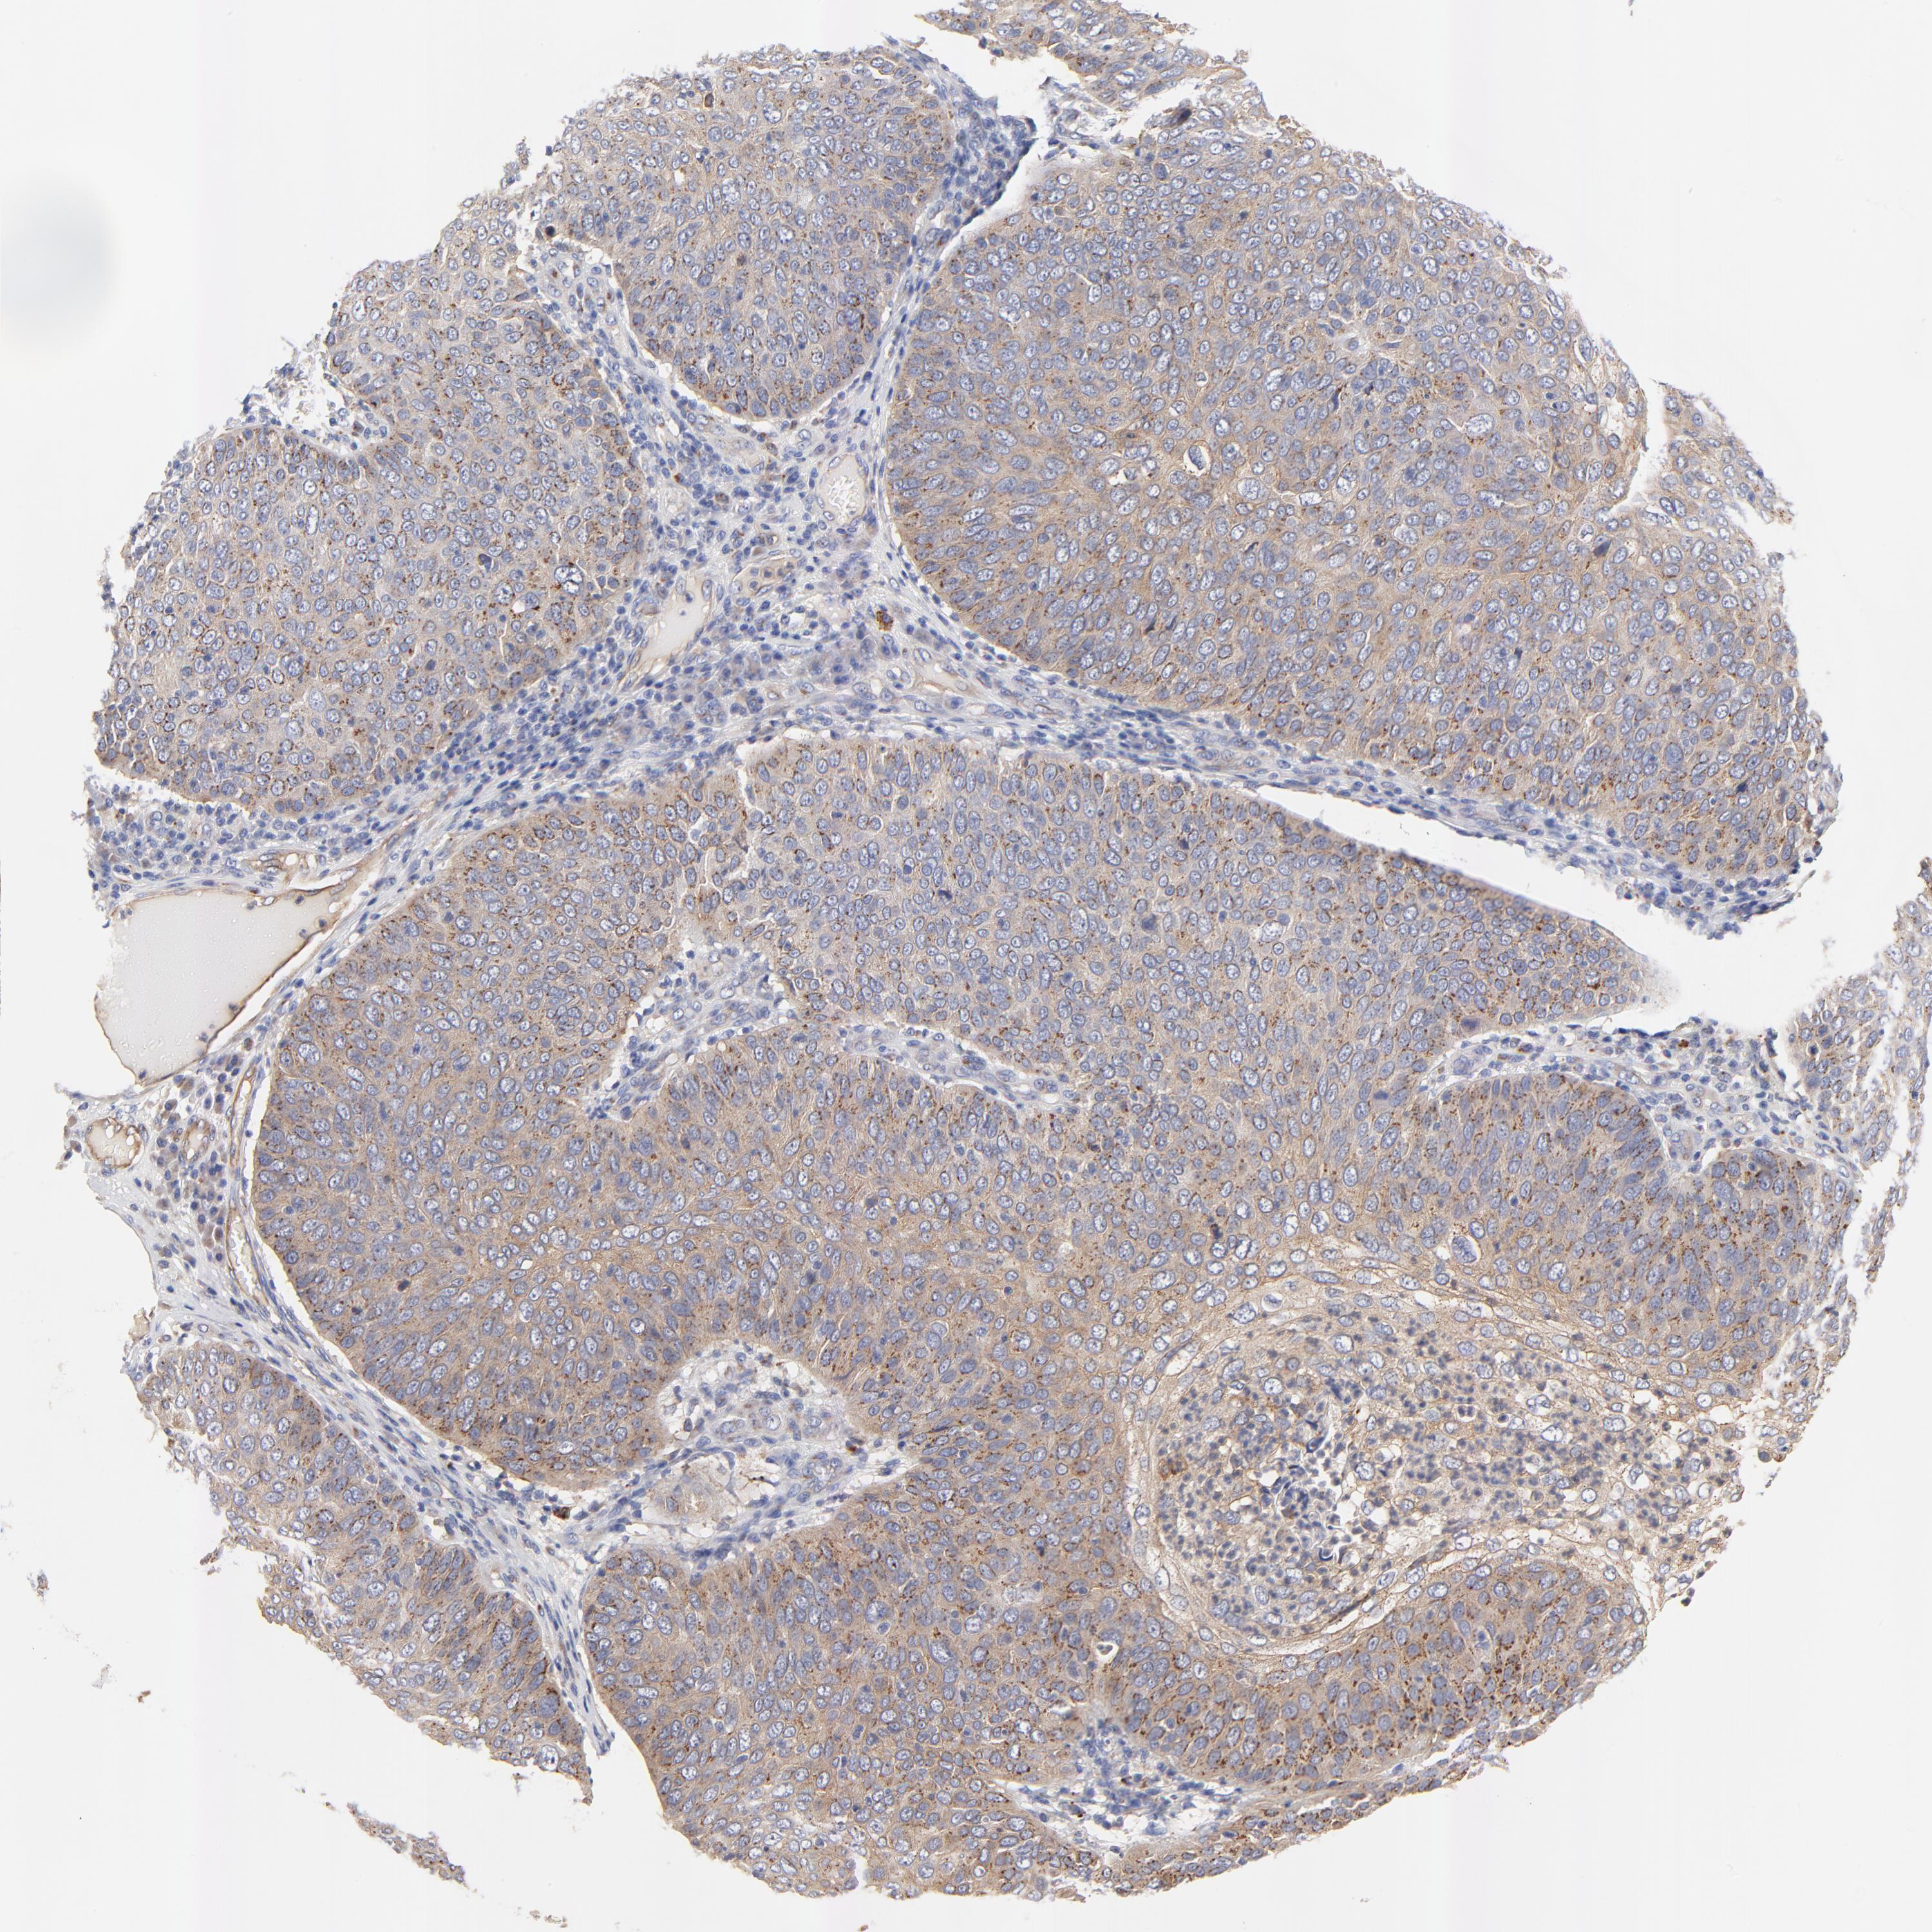

SKIN CANCER - Protein expressioni

A mouse-over function shows sample information and annotation data. Click on an image to view it in a full screen mode. Samples can be filtered based on level of antibody staining by selecting one or several of the following categories: high, medium, low and not detected. The assay and annotation is described here.

Antibody stainingi

Antibody staining in the annotated cell types in the current human tissue is reported as not detected, low, medium, or high, based on conventional immunohistochemistry profiling in selected tissues. This score is based on the combination of the staining intensity and fraction of stained cells.

Each image is clickable and will lead to virtual microscopy that enables deeper exploration of all samples and also displays staining intensity scores, fraction scores and subcellular localization as well as patient and tissue information for each sample.

Antibody HPA003240

Staining

High

Medium

Low

Not detected

Intensity

Strong

Moderate

Weak

Negative

Quantity

>75%

75%-25%

<25%

None

Location

Nuclear

Cytoplasmic/membranous

Cytoplasmic/membranous,nuclear

Squamous cell carcinoma, NOS

Basal cell carcinoma